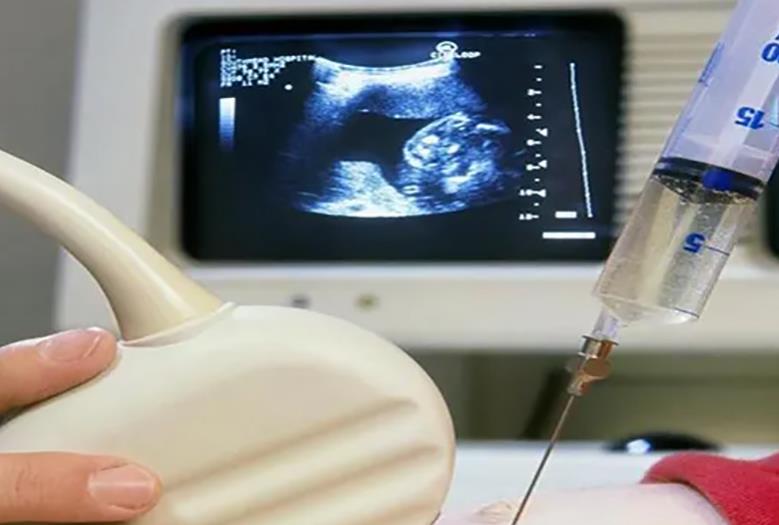

试管婴儿通过药物诱导排卵后取出女方的卵子。多数情况下需要20-40个促排卵药物,预计费用在8000-15000元左右。

不管是人工授精还是试管婴儿,他们的促排卵的过程多多少少的都会有所不同,人工授精是可以促排卵,也可以自然来进行排卵,而食管婴儿必须要选择超出排卵,也就是说他们在做试管婴儿的过程当中会一次性提取20多个卵子,这样的话才能够配置成各种不同的胚胎,从而在无形当中增加试管婴儿成功率,有效降低试管婴儿费用。一次性的促排卵费用,可能价格也在1万元到2万元之间。